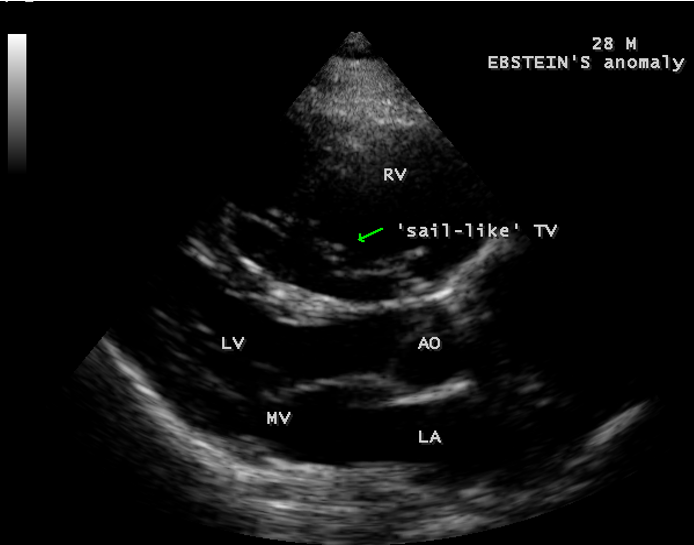

A 28-year old male presented with cyanosis and auscultation revealed a ‘sail sound’ ( loud tricuspid component of first heart sound due to increased tension developed by the large anterior leaflet as it reaches the limits of its systolic excursion- an important sign of anterior leaflet mobility), a ‘cadence’ quality of quadruple rhythm due to wide splitting of first and second sounds ( due to complete right bundle branch block), atrial and ventricular filling sounds (summation of these sounds due to prolonged PR interval). ECG revealed the features of Ebstein’s anomaly as shown in Figures 11 and 12. X-ray chest revealed the Ebstein’s configuration as shown in Figure 13. 2D echocardiography revealed a ‘sail-like’anterior tricuspid leaflet forming a ‘muscular curtain’ in between the inflow and trabecular parts of the right ventricle as an ‘imperforate membrane’ with a ‘pinhole’communication, associated with a muscular VSD (ventricular septal defect) in the proximal, atrialized compartment of right ventricle suggesting an ‘atretic” (‘imperforate’) Ebstein’s anomaly as shown in Figures 14 to 27.

The anterior tricuspid leaflet is not involved in the process of downward displacement, it may be abnormally inserted occasionally and Shiina, et al documented the apical displacement of anterior tricuspid leaflet in 14% of cases echocardiographically [39]. The anterior leaflet forms a large, sail-like intracavitary curtain as in Figures 14, 25 and contains muscular strands instead of consisting entirely of a fibrous membrane as in the normal tricuspid valve [40]. It is potentially mobile with a brisk sail-like movement as shown in Figure 21 to 24 [41], free bloating with a ‘whipping motion’ across the right ventricular outflow tract (RVOT) as shown in Figure 26 and in some cases, the movement is restricted due to its adherence to the ventricular wall as in Figure 1 and 2, 4 and 9. It is often fenestrated, may in part be musculaized , inserting into the trabeculations of the right ventricle (RV) as in Figure 28 and rarely, the anterior leaflet forms an ‘atretic’ membrane that spans the midportion of the right ventricular cavity as in Figure 16.

Valvuloplasty It is favoured if the anterior leaflet is suitable for use as a functional monocuspid valve. The leaflet must exhibit adequate excursion and be free of large fenestrations. If the leaflet is ‘sail-like’ and free and when the tricuspid annulus is markedly dilated, an aggressive “Kay annuloplasty” is preferred as for case 4.